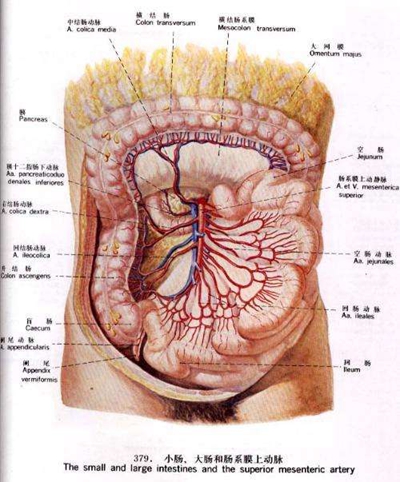

盲腸的位置 (50)

盲腸的位置 (6)

盲腸的位置 (7)

盲腸的位置 (8)

盲腸的位置 (9)

盲腸的位置 (46)

盲腸的位置 (47)

盲腸的位置 (48)

盲腸的位置 (49)

盲腸的位置 (5)

盲腸的位置 (42)

盲腸的位置 (43)

盲腸的位置 (44)

盲腸的位置 (45)

盲腸的位置 (41)

盲腸的位置 (40)

盲腸的位置 (30)

盲腸的位置 (31)

盲腸的位置 (32)

盲腸的位置 (33)